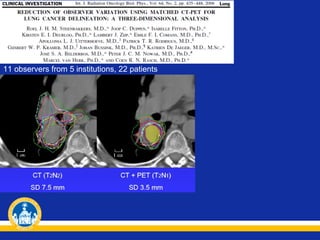

11 observers from 5 institutions, 22 patients

Conclusion: For high-precision radiotherapy, the delineation of lung target volumes

using only CT introduces too great a variability among radiation oncologists.

Implementing matched CT–FDG-PET and adapted delineation protocol and

software reduced observer variation in lung cancer delineation significantly with

respect to CT only. However, the remaining observer variation was still large

compared with other geometric uncertainties (setup variation and organ motion).